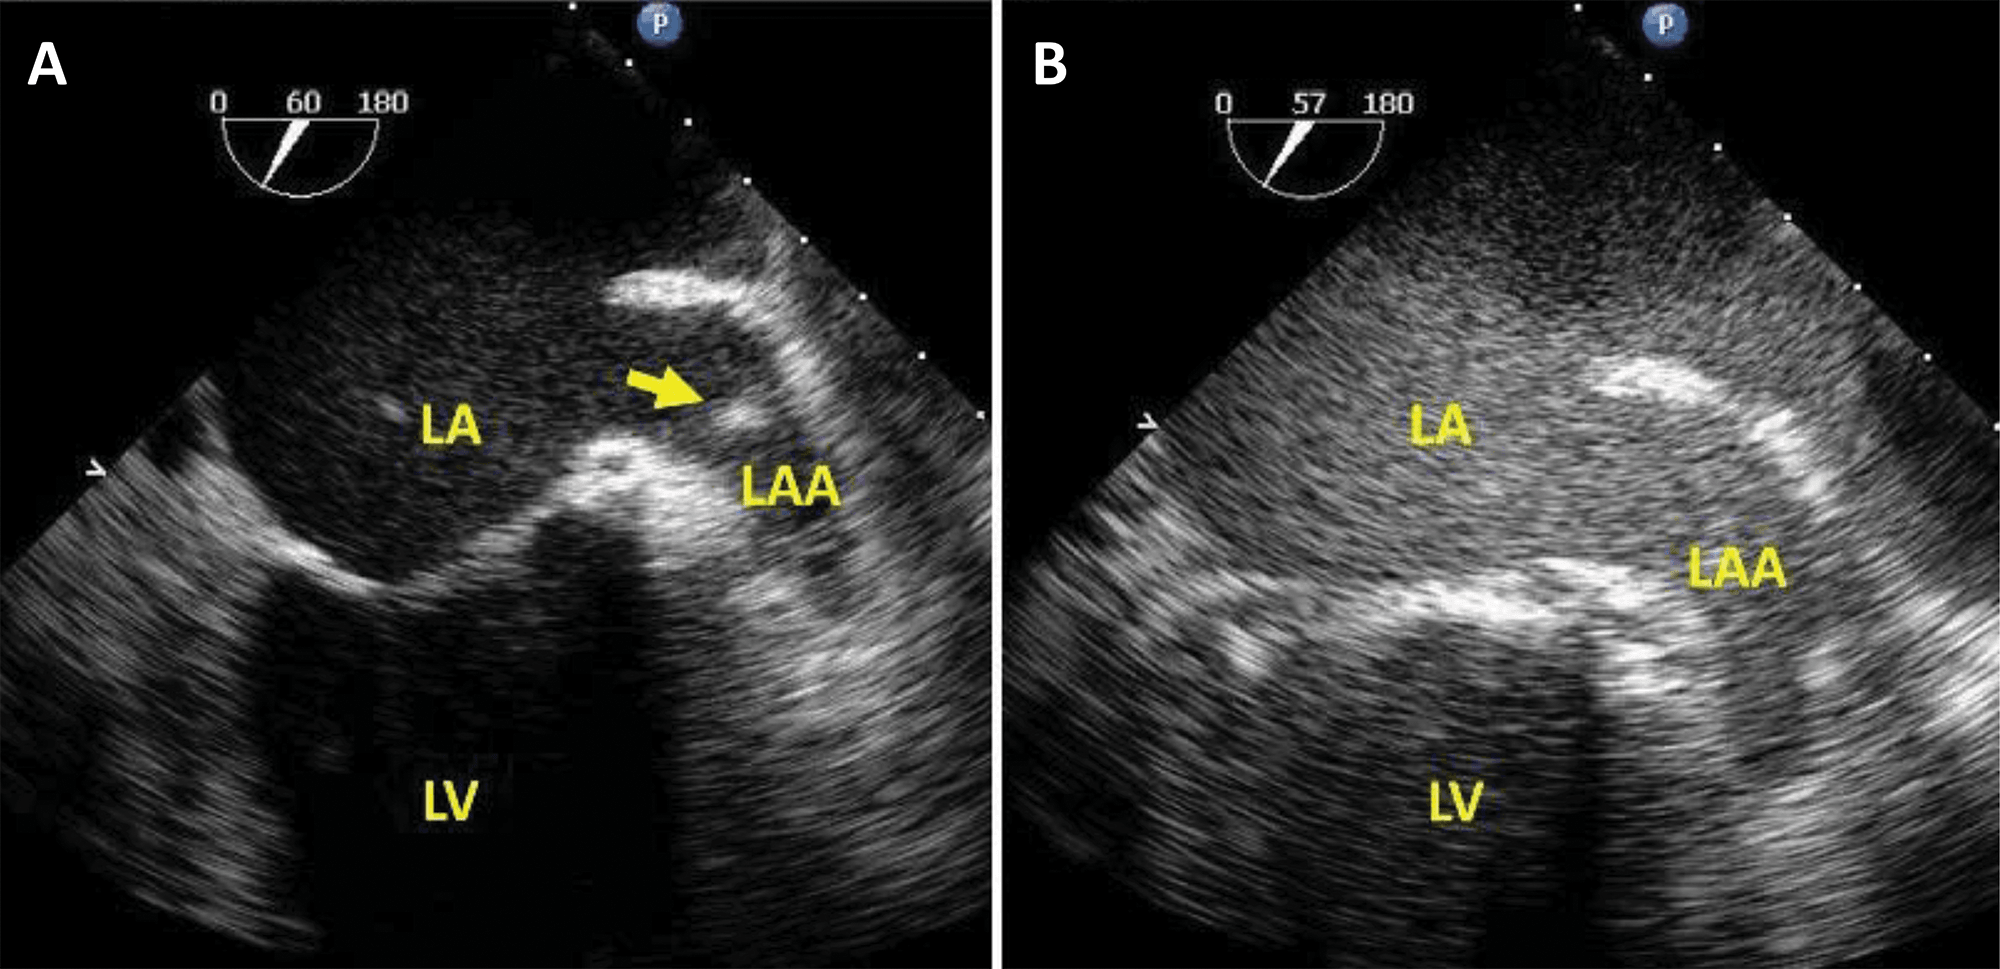

Transoesophageal echocardiography is an established method for assessing the left atrial appendage (LAA) for the presence of thrombi [35, 36] or to guide LAA interventions (Fig. 5, Ref. [36]). In case of LAA stasis, the dense spontaneous contrast may mask the presence of a small thrombus. Several studies demonstrated that the adjunction of UEA increases the diagnostic yield of the procedure [37, 38] and reduces subsequent strokes [39].

Fig. 5.Ultrasound-enhanced TEE used to facilitate the safety of an

atrial fibrillation cardioversion procedure. (A) Mid-esophageal view at

60

However, contrast-specific transoesophageal applications are not available on all ultrasound clinical systems, therefore in such cases non-contrast mode harmonic 2D imaging may be used, with a mechanical index (MI) under 0.3 (Fig. 6, Video 5).